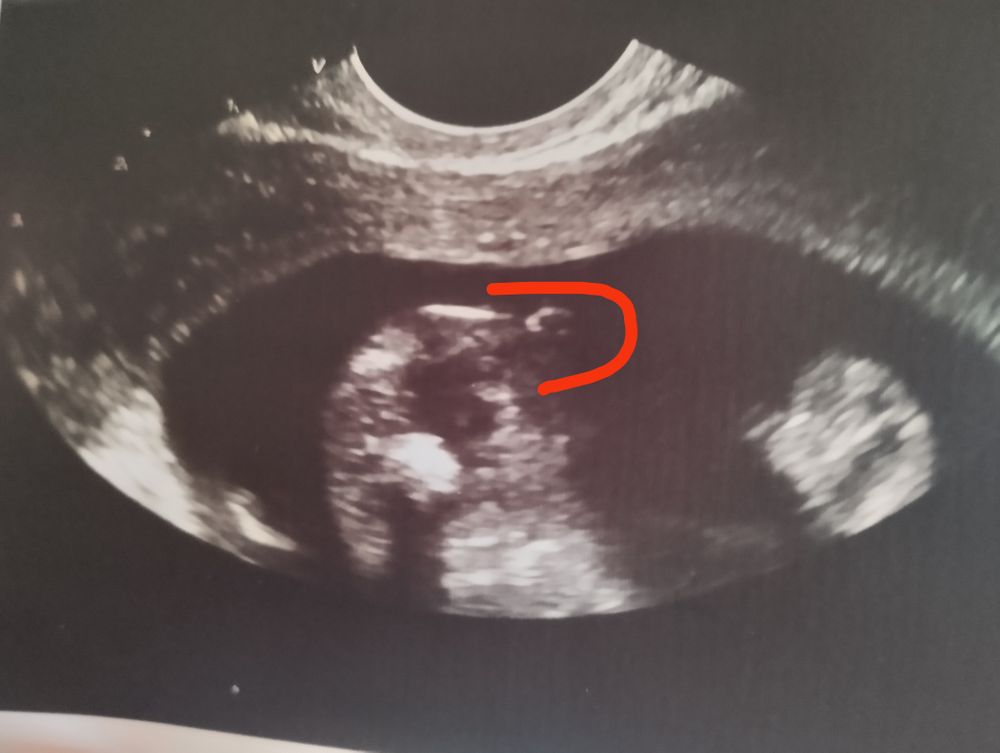

Как думаете, кто там?

То же самое я видела у своей девочки в 17 недель 😂была уверена на 100% что там пацан. До этого у нас 2 пацана ) я жила с этой мыслью до самого гендер пати что это мальчик)) когда узнала что это девочка была в шоке как так 😧там отчетливо видно мальчик 😂

Если в 16 недель не видно мужских признаков -скорее всего девочка!

Девочка

Прикол с полом малыша. Мальчик или девочка?